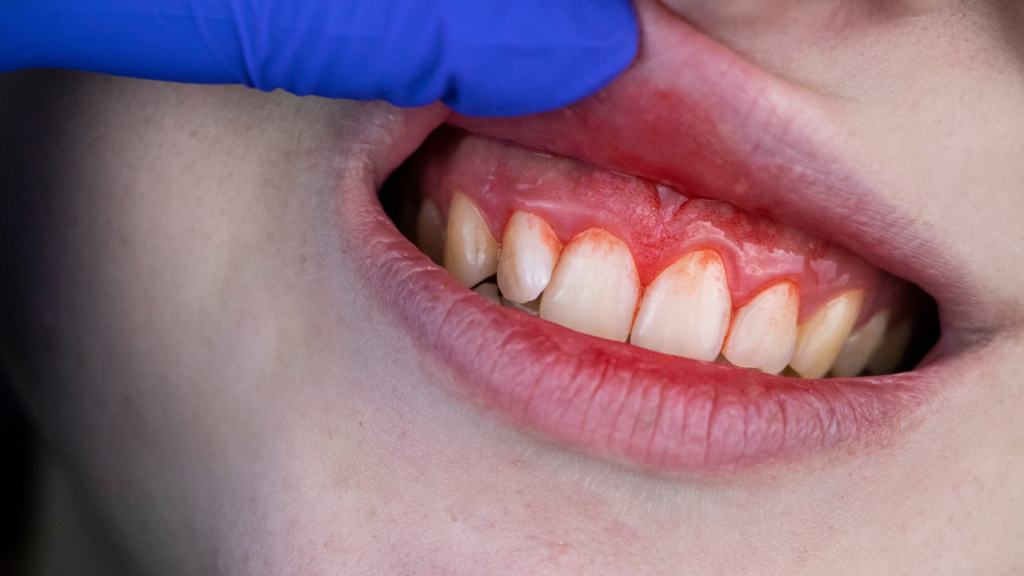

Krwawienie dziąseł jest objawem stanu zapalnego. Najczęściej pojawia się wtedy, gdy tkanki przyzębia reagują na obecność bakterii, płytki nazębnej lub innych czynników drażniących. Dziąsła stają się wtedy przekrwione, obrzęknięte i bardziej podatne na uszkodzenia mechaniczne.

Krwawienie jako sygnał zapalenia

Stan zapalny dziąseł to naturalna reakcja obronna organizmu. Problem pojawia się wtedy, gdy zapalenie utrzymuje się przewlekle. Długotrwałe krwawienie może prowadzić do rozwoju zapalenia przyzębia, a w konsekwencji do rozchwiania, a nawet utraty zębów.

Prawidłowo funkcjonujące dziąsła są jędrne, różowe i ściśle przylegają do zębów. Nawet intensywne szczotkowanie nie powinno powodować krwawienia. Jeśli pojawia się krew, oznacza to, że struktura tkanek została osłabiona przez stan zapalny lub inne czynniki.